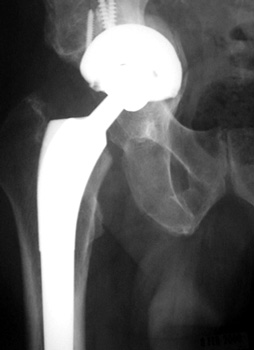

No prior studies available. Abnormally widened interfaces about femoral component at Gruen zones 1, 6, and 7. Osteolysis at Gruen zone 5 with marked thinning of femoral cortex placing patient at risk for pathologic fracture.

Cement fracture Gruen zone 6 close up next slide

CEMENT FRAGMENTATION

May occur with shift of femoral component.

Transverse fractures of cement near distal femoral stem seen in up to 1.5% of THR, associated with mild subsidence. If less than 4mm, usually not associated with failure. (Weber and Charnley)